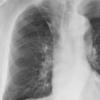

Normal PA Female

Date: 12/06/2014

Views: 6013